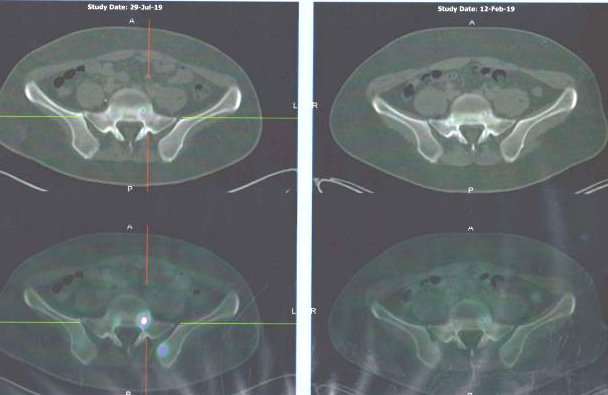

Something wrong with the bones? Scan on 29 July 2019 (left column) seemed to be more serious than scan done on 12 Feb 2019 (right).

Did the cancer go away after all the treatments?

Again, ask this question: From the above, do you see any improvement? And what had scientific, modern medicine done to him? Study what the reports carefully and you will know the answers.